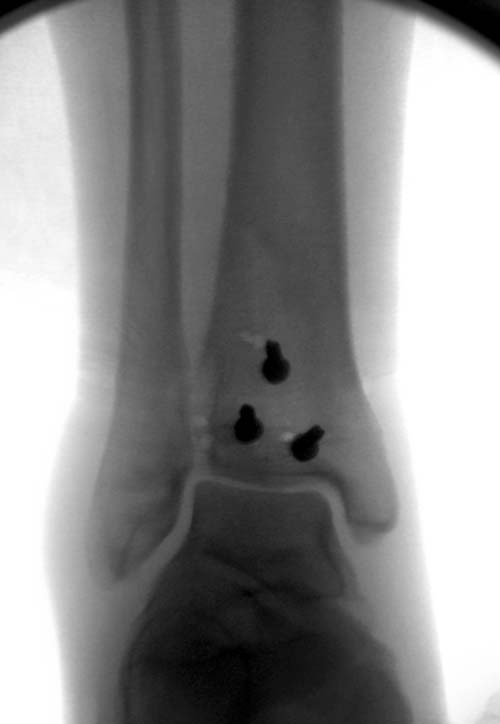

Второй случай в результате скоростной травмы, кроме пилона, вовлечение других органов! Отек при поступлении и открытый перелом на другой стороне. В таких случаях нет смысла спешить, и временный наружный фиксатор на несколько дней. После спадения отека фиксация передне-наружной пластиной. Реабилитация - ранние движения, без нагрузки.